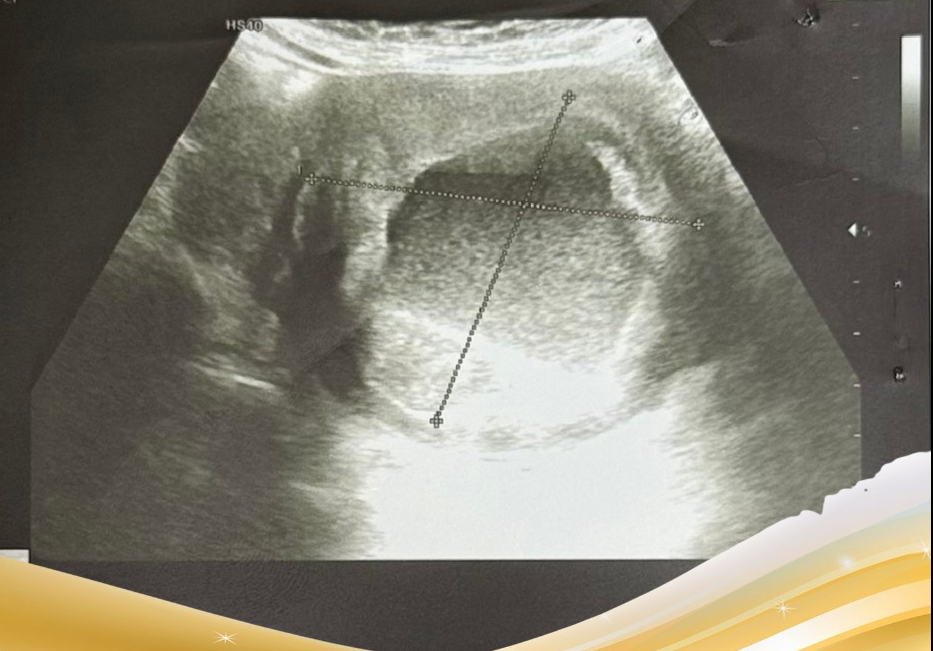

Gần đây, những cơn đau tức hạ vị xuất hiện dồn dập. Kết quả thăm khám gây bất ngờ: Khối u không hề nhỏ đi mà có kích thước rất lớn 81x87mm, kết quả chụp MRI cho thấy: Hình ảnh khối u xơ lớn ở thân tử cung (FIGO 2-5), có hoại tử dịch hóa – xuất huyết trung tâm. Khối u xơ thành trước tử cung (FIGO 6).

Hình ảnh khối u trên siêu âm - Ảnh BVCC